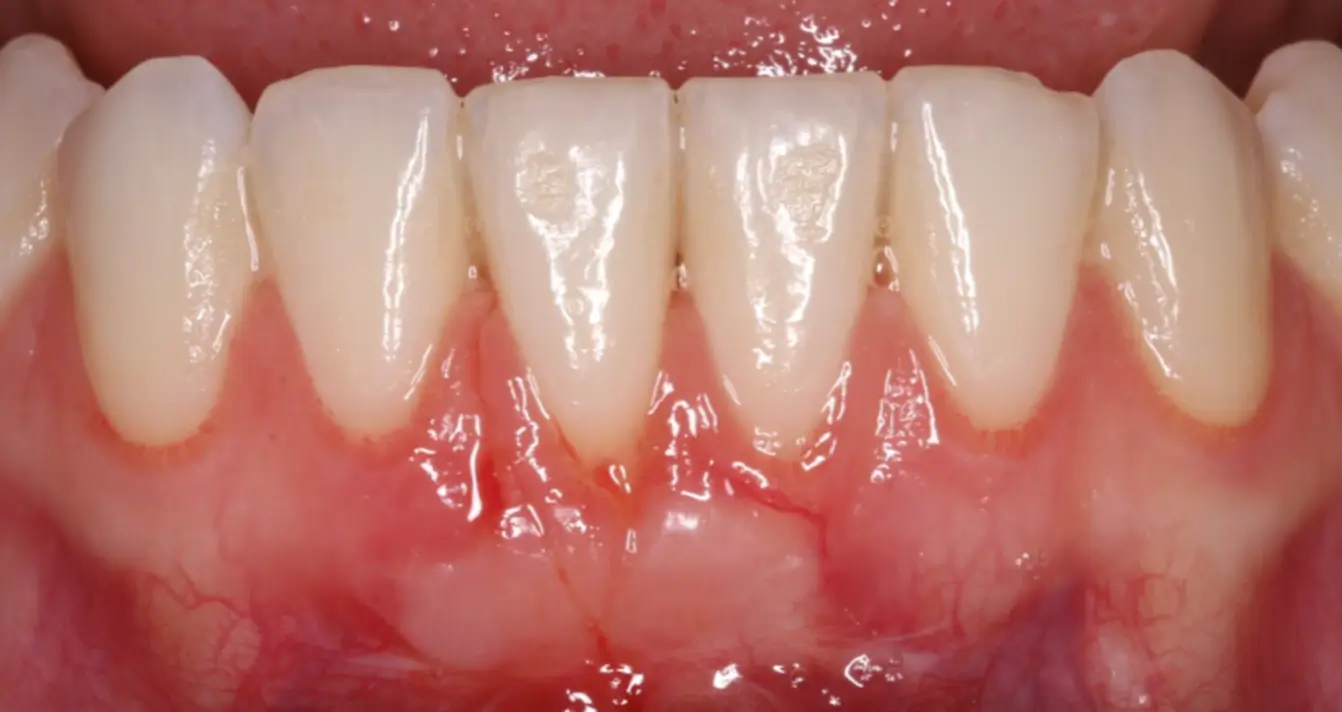

Connective Tissue Graft

before

after